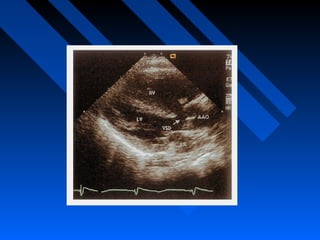

ECHOCARDIOGRAPHY

 2-D echocardiography cornerstone for noninvasive diagnosis.

 Doppler analysis provides further data regarding

hemodynamic characteristics.

 The coronary arteries are also readily apparent in PSAX view

slightly superiorly.

 The origin and course of the left and right coronary arteries

should be determined, paying special attention to whether any

vessels take an anterior course across the infundibulum.

 Correct definition of the coronary artery anatomy was possible

in most patients with a sensitivity of 82%, specificity of 99%,

and accuracy of 98.5% in a study by Need et al.

ECHOCARDIOGRAPHY  2-D echocardiographycornerstone for noninvasive diagnosis.  Doppler analysis provides further data regarding hemodynamic characteristics.  The coronary arteries are also readily apparent in PSAX view slightly superiorly.  The origin and course of the left and right coronary arteries should be determined, paying special attention to whether any vessels take an anterior course across the infundibulum.  Correct definition of the coronary artery anatomy was possible in most patients with a sensitivity of 82%, specificity of 99%, and accuracy of 98.5% in a study by Need et al.